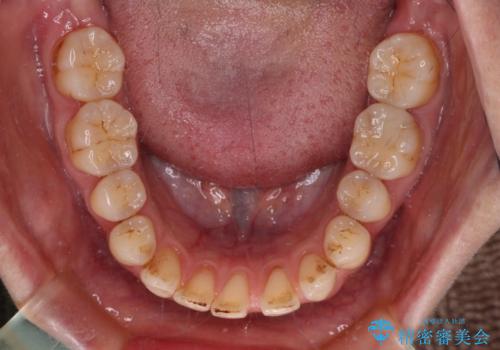

- 上下前歯の隙間を気にして来院された患者様です。

下顎前歯が1本欠損しており、上下小臼歯はクロスバイトとなり、上下前歯の接触もないという不正咬合の状態でした。

クロスバイトはワイヤー矯正が得意とするところであり、上下前歯の非接触や開咬はインビザラインの得意とするところであるので、ワイヤー装置により事前にクロスバイトを改善し、その後にインビザラインにて仕上げていくこととしました。

奥歯の咬み合わせに問題がある場合、インビザラインでは改善できないことが多々あります。事前にワイヤー装置により問題点を解消しておくことで、スムーズにインビザラインでの矯正治療を進めていくことができます。